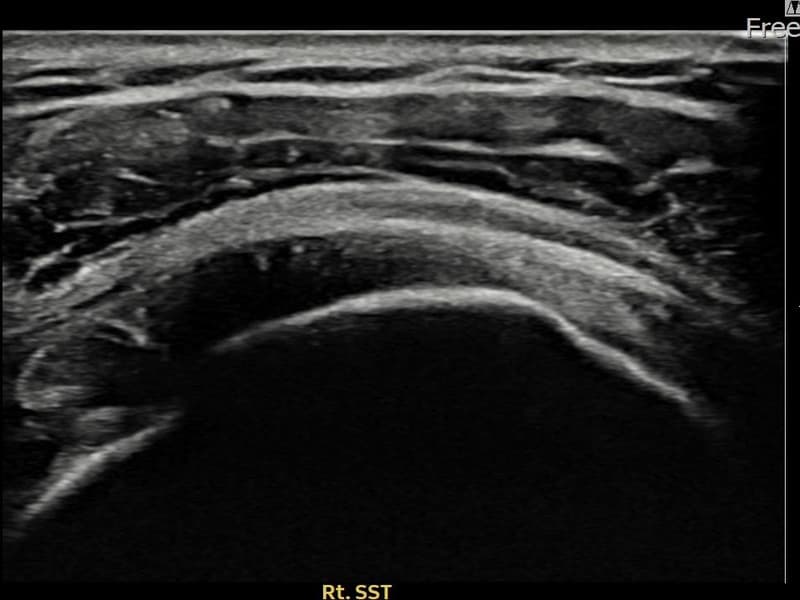

术前

术前超声确认右侧 冈上肌腱 关节面侧部分撕裂,右侧冈上肌腱回声不连续伴肌腱缺损(9mm × 4mm (肌腱厚度约38%缺损))。术后超声显示撕裂部位充满再生组织,肌腱连续性恢复,回声模式正常化。